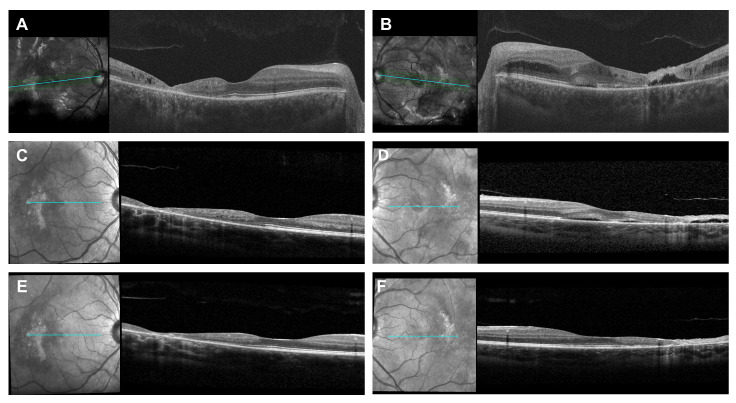

Purpose: To report a case of cystoid macular edema (CME) secondary to immune recovery uveitis (IRU) in a patient with previous history of cytomegalovirus (CMV) retinitis and leukemia, which was successfully treated with tocilizumab (TCZ), an interleukin-6 (IL-6) receptor antagonist. Method: The clinical records of the case were reviewed, focusing on demographics, image findings, and clinical course. Results: A 17-year-old female with a past medical history of T-cell acute lymphoblastic leukemia (T-ALL) undergoing chemotherapy for two years presented with active CMV retinitis. She was successfully treated with intravitreal foscarnet injections and systemic ganciclovir. After 5 months of systemic valganciclovir maintenance and following cessation of chemotherapy, the patient developed bilateral CME and vasculitis, and was diagnosed with IRU. CME management was challenging due to a history of bilateral avascular necrosis of the femoral head resulting from prolonged systemic corticosteroid use. Two cycles of monthly TCZ infusions were administered at the dosage of 8mg/kg. Subsequently, the CME and retinal vasculitis resolved significantly without any evidence of inflammation in the anterior chamber and vitreous. Conclusion: The index case report demonstrated the safety and efficacy of the IL-6 receptor antagonist TCZ in treating CME associated with IRU in a non-HIV CMV retinitis patient.